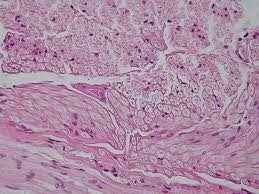

TEJIDO ÓSEO

El tejido óseo es un tipo especializado de tejido conectivo cuya matriz está mineralizada con sales de calcio y fósforo, lo que le confiere rigidez y resistencia.

Constituye la parte sólida del esqueleto, proporciona sostén, protección, movimiento, almacenamiento mineral y participa en la formación de células sanguíneas dentro de la médula ósea.